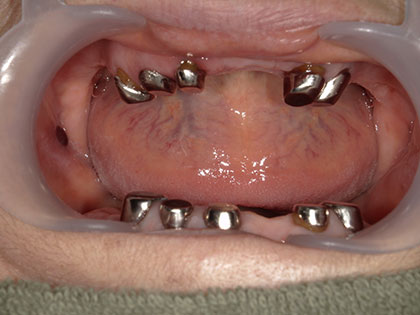

• 今回は上下に5か所ずつマグネットを装着し、その上に金属床義歯を上下にセットしました。

• 入れ歯の下に自分の歯があり、磁石が入ることにより入れ歯が食事の際に外れたり、沈み込みがなくなり、よく噛めるようになります。

• 入れ歯が食事中や会話中に外れる事はなくなります。

• 磁石なのでピッタリフィットします。

• 強い力で噛めます。

• 歯肉だけでなく、磁石を付けた歯でもカバー出来るので、よく噛めます。